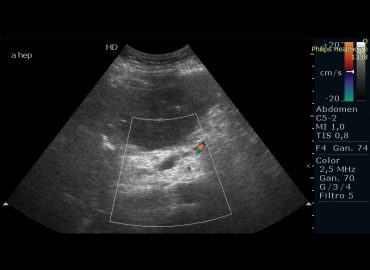

Motivo de consulta: Dolor abdominal